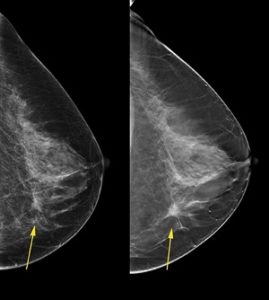

“This simple blood test, used in combination with mammography, can be a transformative tool in the fight against breast cancer by determining whether cancer is present in the breast and whether the cancer is likely to spread.” Sims-Mourtada said. “Using this test could minimize over-diagnosis and treatment while potentially providing significant savings in healthcare related costs. Studies have shown that mammograms alone are not optimal for diagnosing all types of breast cancer.”

“This test is designed to monitor epigenetic DNA changes in the blood cells that could signal an early stage aggressive tumor,” Sims-Mourtada said. “We know that immune cells in the blood react differently if they are all responding to an infection versus a cancer, an invasive tumor or when there is no cancer present at all.”

“Right now there is no truly effective method for routine monitoring of patients to follow in response to treatment for breast cancer and for possible recurrence of cancer,” Sims-Mourtada said. “Using the assay we have developed, in conjunction with routine monitoring enables us to follow changes in the immune response to detect an increase in tumor cells over time. This test can allow for much earlier detection of recurrence or metastatic disease before it is visible with standard imaging and enable much earlier treatment.”